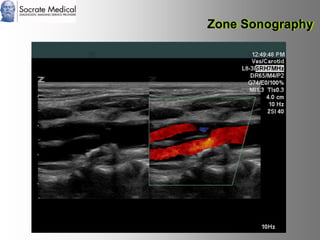

Il documento presenta la tecnologia della zone sonography, che promette una rivoluzione nel campo degli ultrasuoni, superando i limiti dei sistemi tradizionali grazie a metodi di acquisizione dati più veloci e una gestione delle informazioni migliorata. Questa tecnologia consente una maggiore definizione dell'immagine, una riduzione degli artefatti e un'ottimizzazione del processo diagnostico, con vantaggi in termini di tempo e costi. Inoltre, il channel domain processing e la zone speed technology offrono applicazioni avanzate e miglioramenti nella sicurezza diagnostica.